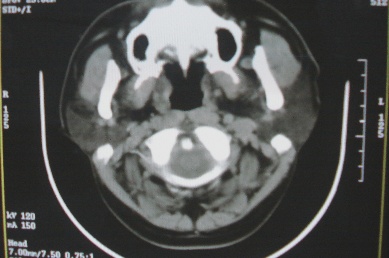

ct10755,男,28岁。发现左侧腮腺区肿块几年,今要求ct检查。左侧腮腺区低密度影,ct值-153hu。

左侧腮腺区囊状低密度影,ct值-153hu,考虑腮腺脂肪瘤。

病灶为一边界清晰脂性区,其内未见实质性组织.支持考虑:左侧腮腺脂肪瘤可能性大.

ct能定性的良性肿瘤不多,对脂肪瘤的诊断是比较有把握的,加大窗宽还可以看到里面有分隔

ct值-153hu,腮腺脂肪瘤。